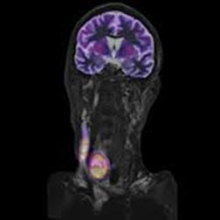

FDG-PET/MRI comparable a FDG-PET/CT en cáncer de cabeza y cuello

Los estudios de FDG PET/MRI pueden producir imágenes de calidad diagnóstica comparable a aquellas de los estudios de FDG PET/CT en pacientes con cáncer de cabeza y cuello, de acuerdo a un estudio presentado durante el Congreso Europeo de Radiología llevado a cabo en Viena, Austria en marzo de este año. Investigadores de la Universidad de Leipzig en Alemania no hallaron diferencias estadísticamente significativas en lo que respecta a sensibilidad, especificidad y valores predictivos positivo y negativo entre las dos modalidades híbridas.

Las imágenes PET por sí solas mostraron la mayor sensibilidad (96%), mientras que las imágenes de MRI mostraron la mayor especificidad (96%). Basados en esta pequeña muestra de 17 pacientes, Stumpp y colegas concluyeron que el FDG PET/MRI es comparable al FDG PET/CT para detectar tejido tumoral en cáncer de cabeza y cuello, pero recalcaron la necesidad de estudios más extensos para confirmar sus resultados.

En realidad, el objetivo de este estudio prospectivo y transversal fue demostrar la no inferioridad del PET/MRI contra el PET/CT en esta aplicación clínica. El cáncer de cabeza y cuello es una de las indicaciones potencialmente relevantes para el PET/MRI, debido a que estos tumores, por su patrón de diseminación comprometen de forma importante los tejidos blandos (los cuales son de difícil valoración con CT), de tal manera que se perfila como una modalidad híbrida que proporcionaría información más precisa al momento de la estadificación y re-estadificación de estos pacientes. Otros tipos de cáncer en los que el PET/MRI podría exhibir utilidad clínica superior son los sarcomas y el cáncer de próstata.